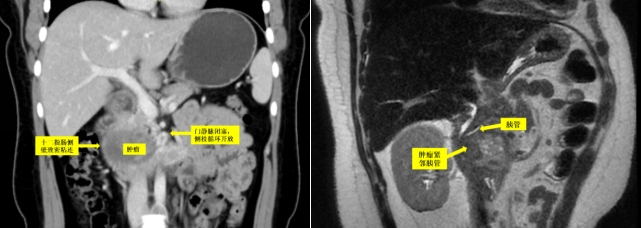

主任医师李虎城接诊阅片后,初步判断患者胰头肿物为囊实性混杂成分,初步考虑为实性假乳头状瘤,介于良性和恶性之间,手术切除是唯一可以治愈的手段。并且患者肿瘤距离胆管、胰管都非常近,导致解剖严重移位,门静脉、肠系膜上静脉已经完全闭塞,与肿瘤融为一体,门脉系统侧枝循环静脉开放,肿瘤还向右侧明显挤压十二指肠导致肠腔狭窄,建议马上收住院完善相关检查,为患者争取适宜手术时机。

手术当天,先由黄鑫医师行十二指肠镜下胰管支架植入术,以避免胰管损伤。李虎城、王学栋、王鹏飞三位医师密切配合,腹腔镜下钝锐结合仔细分离肿瘤与周围组织的致密粘连,将门静脉从肿瘤左侧完整游离出来,术中可见门静脉已经明显纤维化,完全闭塞。再于肿瘤外侧将十二指肠剥离下来,见十二指肠浆膜已大面积损伤。两处门静脉出血予以镜下精准缝扎,镜下行下腔静脉破损缝合,同时完整修补破损的十二指肠浆肌层,完整切除肿瘤,术中失血50毫升。术后患者恢复顺利,由于患者十二指肠之前已有大范围损伤,术后第10天才开始恢复饮食。未出现出血、胆漏、胰漏等并发症,先后顺利拔出胰管支架、拔除腹腔引流管,于近日顺利出院。至此,那场“无法做的手术”顺利破冰,腹腔镜、十二指肠镜双镜联合的杂交手术圆满落下帷幕。